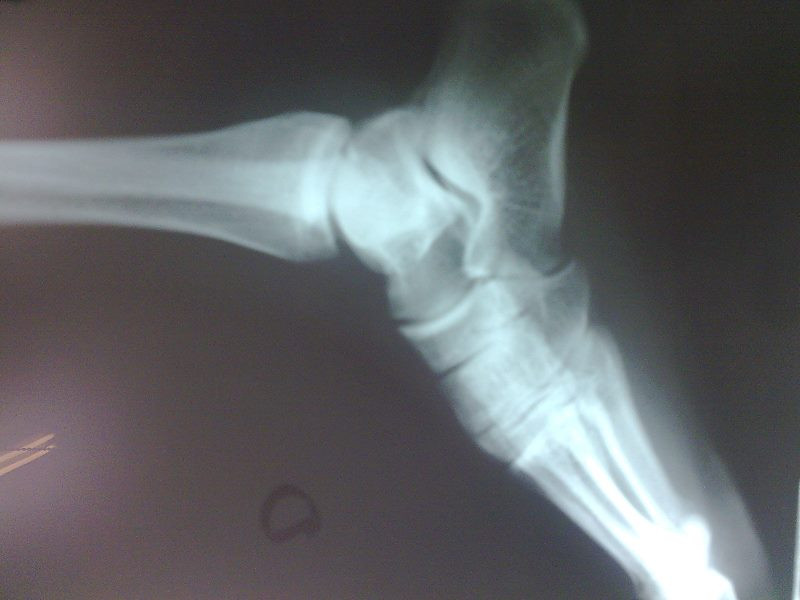

Radiografías con enfoque en fisiatría

Envíado por Dr. Hernán Darío Sánchez Ramos